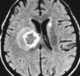

Neurocysticercosis is a specific form of the infectious parasitic disease cysticercosis that is caused by the infection with Taenia solium, a tapeworm found in pigs. Neurocysticercosis occurs when cysts formed by the infection take hold within the brain, causing neurologic syndromes such as epileptic seizures. [Source: Wikipedia ]